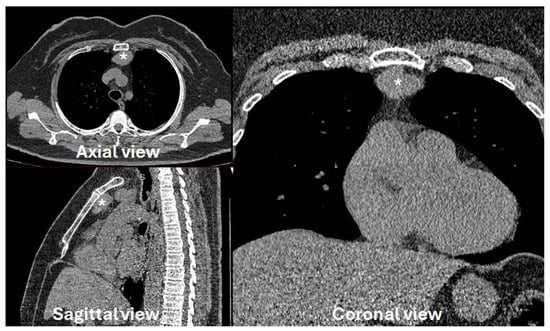

Comparative Study of Radiologic Changes in Ulnar Variance and Ulnolunate Distance After Distal Radius Fracture Surgery: Patients with vs. Without Lunate Ulnar Corner Cysts

Surgeries 2026, 7(1), 39; https://doi.org/10.3390/surgeries7010039 - 17 Mar 2026

Background: Subchondral cysts at the ulnar corner of the lunate are frequently encountered in patients with distal radius fractures. We hypothesized that the presence of these lunate subchondral cysts may be associatedwith decreased cortical bone density due to limited load translation. Consequently, this

Background: Subchondral cysts at the ulnar corner of the lunate are frequently encountered in patients with distal radius fractures. We hypothesized that the presence of these lunate subchondral cysts may be associatedwith decreased cortical bone density due to limited load translation. Consequently, this could lead to lunate fossa collapse and increased ulnar variance following fracture fixation. Methods: A retrospective analysis was performed on 176 patients who underwent open reduction and internal fixation using the Double-tiered Subchondral Support (DSS) procedure between May 2014 and June 2017. Twenty-eight patients identified with lunate subchondral cysts on preoperative CT scans were selected as the study group. A control group of 28 patients without cysts was selected using matched-pair analysis, controlling for gender, age, fracture classification, and follow-up period. Results: The mean change (delta) in ulnar variance was 0.191 mm in the cyst group, which was less than the 0.233 mm observed in the control group; however, this difference was not statistically significant (p = 0.557). Regarding ulnolunate distance, the cyst group showed a mean change (delta) of 0.991 mm, while the control group showed a change of 1.123 mm. This difference was also not statistically significant (p = 0.681). Conclusions: Although it was hypothesized that lunate subchondral cysts might limit load translation to the radius and compromise cortical bone density—potentially affecting fracture healing and the maintenance of reduction—our statistical analysis did not support this hypothesis. The presence of lunate subchondral cysts did not significantly increase the risk of lunate fossa collapse or ulnar variance progression compared to the control group.